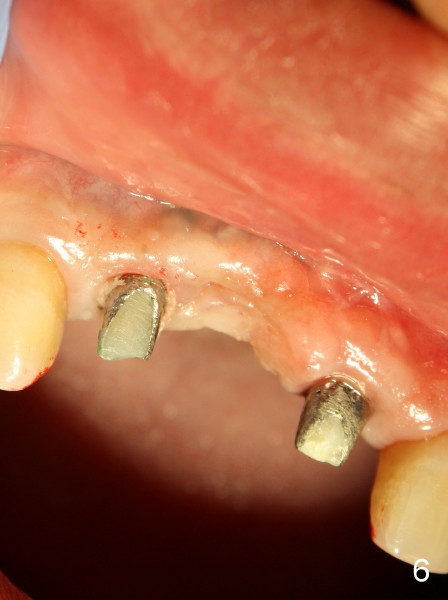

This time PFM FPD was fabricated with lingual metal as shown in Fig.4. The bridge was temporarily cemented on Feb. 09, 2011. Night guard was fabricated later. Unfortunately the bridge came off 7 months later and was recemented temporarily. Permanent cementation was not attempted, because of potential porcelain chip or implant/abutment screw loosening due to bruxism. Yesterday, the patient reported that the bridge was loose again. Today, #7 build-up changed from loose, disintegrated Cavit to more solid composite (Fig. 5 to 6). The bridge was cemented temporarily to avoid porcelain chip related to permanent rigid cementation. Fig.7 shows occlusal equilibrium after cementation. The patient felt that there was no premature contact to the bridge. What should we do next? Can we add an implant at the site of #8. Can this alleviate bruxism-related problems (easy decementation, porcelain chip and possible loosening of screw between abutment and implant)? Thanks.